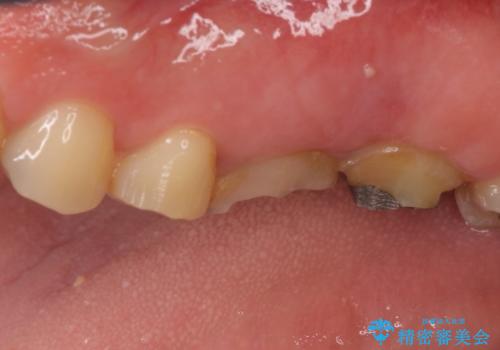

- 長い間虫歯を放置しており、違和感を感じ始めてきたので治療を開始したいと来院された患者様です。

極力抜歯が回避する方法を選択して診察を開始しましたが、1本は保存困難と判断されたため、フルジルコニアブリッジによる補綴治療を行うこととしました。

違和感を感じていた歯は虫歯が非常に大きく、骨に到達するほどの穴が空いていました。

抜歯をしたことで違和感はなくなり、ブリッジを装着したことでしっかりと噛めるようになり、患者様には大変満足していただきました。